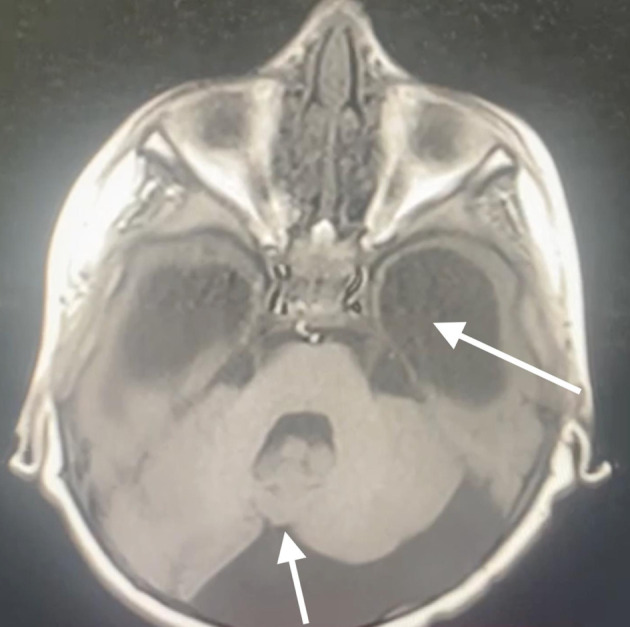

Dandy-Walker综合征是一种罕见的后窝先天性畸形,具有独特的麻醉挑战,包括气道管理困难、意识改变、脑积水和术后通气时间延长的可能性。脑积水是最常见的症状,可使通气和插管复杂化,而脑干受累,以及胼胝体发育不全、脑桥发育不全和髓质呼吸中心扭曲,可能导致术后通气时间延长。这种情况下的麻醉管理需要彻底的气道评估,为潜在的气道困难做准备,颅内压监测和控制,以及全静脉麻醉(TIVA)以促进快速急救。我们描述了一例3岁男性大头畸形、运动障碍、认知发育迟缓和精神状态改变的病例,在没有肌肉松弛剂的情况下,在仔细的气道准备和颅内压控制下,计划在TIVA下放置脑室-腹膜分流术。据我们所知,这是首例用这种方法治疗Dandy-Walker综合征的病例。

Dandy-Walker syndrome is a rare congenital malformation of the posterior fossa that presents unique anesthetic challenges, including difficult airway management, altered consciousness, hydrocephalus, and potential for prolonged postoperative ventilation. Hydrocephalus, the most common finding, can complicate ventilation and intubation, whereas brainstem involvement, along with agenesis of the corpus callosum, pontine hypoplasia, and distortion of the medullary respiratory centers, may contribute to prolonged postoperative ventilation. Anesthetic management in such cases requires thorough airway assessment, preparation for potential airway difficulties, intracranial pressure monitoring and control, and total intravenous anesthesia (TIVA) to facilitate rapid emergence. We describe the case of a 3-year-old male with macrocephaly, movement disorders, delayed cognitive development, and altered mental status, scheduled for ventriculoperitoneal shunt placement under TIVA without muscle relaxants, with careful airway preparation and intracranial pressure control. To our knowledge, this is the first reported case of Dandy-Walker syndrome managed in this manner.